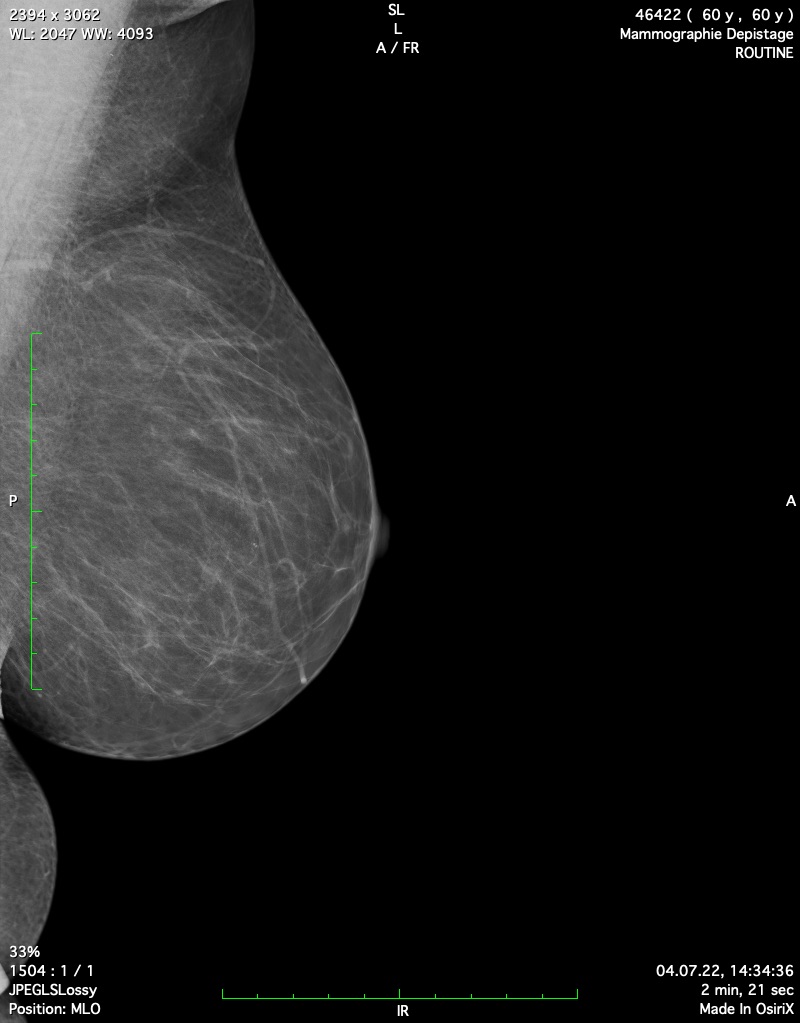

Il existe des situations dans lesquelles la lecture des mammographies par le radiologue est plus complexe. Cela est notamment le cas lorsqu’une femme présente des seins denses.

Le sein est en effet composé de trois types de tissus : le tissu graisseux, moins épais, et les tissus glandulaires et fibreux. Avoir des seins denses signifie qu’ils sont composés d’une plus grande quantité de tissus glandulaires et fibreux que de graisseux.

Sur une mammographie, les tissus denses apparaissent en blanc, tout comme les tumeurs. Ceci explique que des seins denses rendent la lecture des images plus difficile.